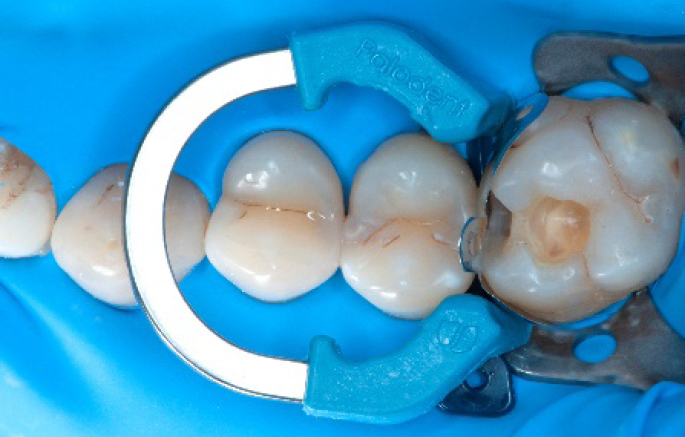

Step 1:

The situation after rubber dam isolation.

Step 2:

Initial cavity preparation, protecting the adjacent tooth with a Palodent1 WedgeGuard.

Step 3:

Class II cavity prepared.

Step 4:

The complete Palodent1 system in place: sectional matrix, wedge and ring.

Step 5:

Buccal view of the Palodent1 system.